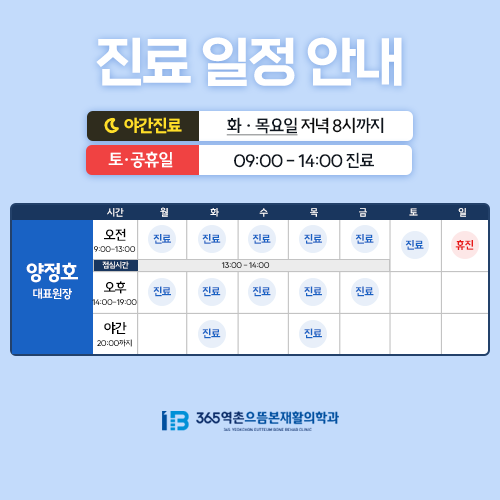

화·목 야간진료 / 공휴일 진료

화·목 야간진료 / 공휴일 진료

화·목 야간진료 / 공휴일 진료

진료시간

- 월·수·금 AM 09:00 ~ PM 07:00

- 화·목 AM 09:00 ~ PM 08:00

- 토요일 AM 09:00 ~ PM 02:00

- 점심시간 PM 01:00 ~ PM 02:00

- 토요일 점심시간 없음

- 일요일 휴진